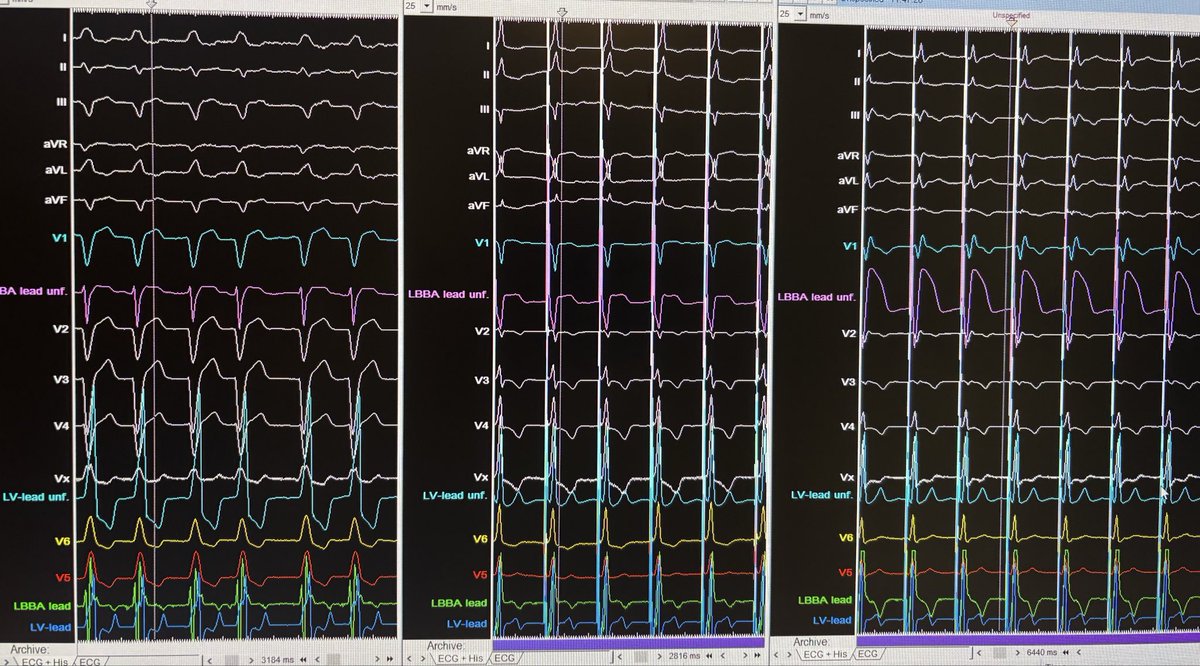

Another day at the cathlab. Pt with LBBB sent to me for P&A by @Dominik_Linz. Temp HBP shows correction and ns/s-LBBP obtained with 3830 lead. “Simply lovely” as Max Verstappen would say (@Max33Verstappen) @curilakarol @DrRoderickTung @Marek_Jastrz_EP @Hisdoc1 @gauravaupadhyay